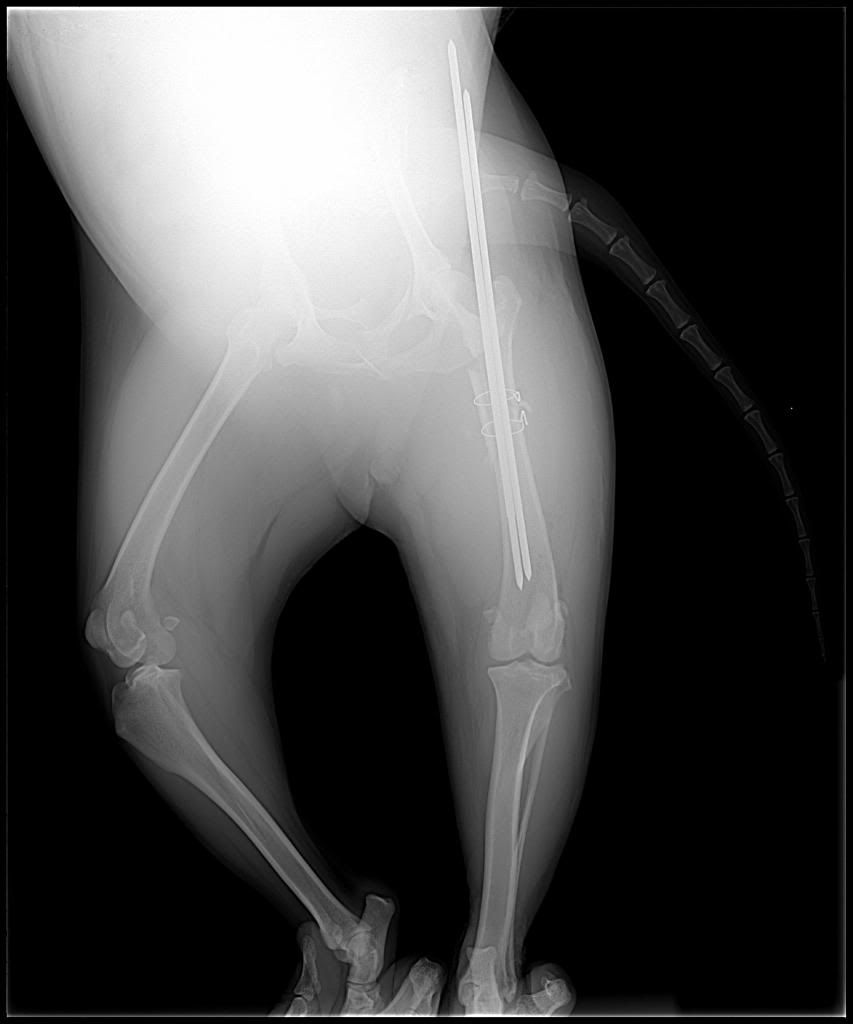

As some of you may recall from previous threads about dogs in public places, I have a service dog. Last Saturday she snuck out of the house while we were doing a kitchen renovation and got hit by a car. We were very lucky that the lady who hit her stopped and came looking for us, since my dog may have died of shock before we ever realized she was missing. Anyway, her back leg was broken into three pieces, but there was nothing else wrong with her (no internal bleeding or head trauma). Still, the emergency vet was telling us it would cost $3,000-$5,000(!) to fix her leg.

Then I found the people at James Landing Veterinary Hospital. Their first concern was that my dog was comfortable and the first thing they wanted from me were her x-rays. They promised that they would do everything they could to take care of my dog, and they have. Because she's my service dog they cut the price to a third of what every place else was quoting: a difficult price to pay but not impossible with the help of friends and family. They sent me that day to their sister clinic, the Thomasville Veterinary Hospital. She got her surgery Tuesday and is doing well. We expect to have her home late next week and the vet says she'll have a full recovery! They even think her leg will be strong enough for her to perform her mobility work of helping me get up off the ground if I fall.